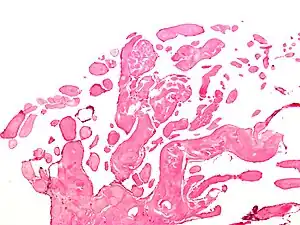

| Micrograph of a papillary fibroelastoma, a benign tumor of heart valves. H&E stain. | |

- Papillary Fibroelastoma

A subset of the primary tumors of the heart are tumors that are found on the valves of the heart. Tumors that affect the valves of the heart are found in an equal distribution among the four heart valves.[2] The vast majority of these are papillary fibroelastomas. Primary tumors of the valves of the heart are more likely to occur in males. While most primary tumors of the valves of the heart are not malignant, they are more likely to have symptoms related to the valve, including neurologic symptoms and (in a few cases) sudden cardiac death.